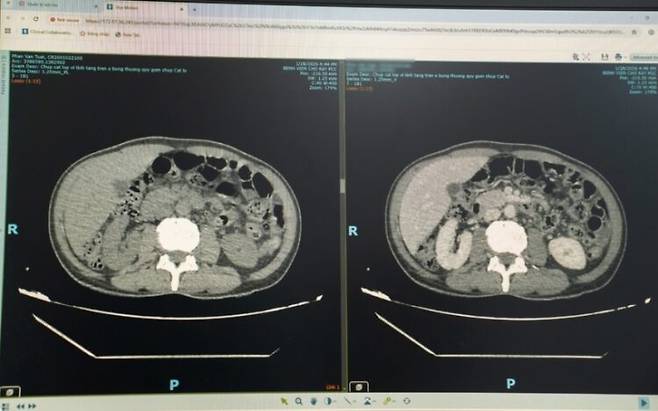

이 남성은 복부 초음파 검사를 받았고, 그 결과 간 농양이 발견됐다. 추가 검사와 정밀 영상 검사를 통해 간을 관통하는 6~7cm 길이의 이물질이 확인됐다. 의료진은 이물질로 인한 간 농양을 진단했다. 의료진은 "이물질이 체내로 들어가 소화관을 뚫고 간으로 이동해 국소 감염과 농양을 유발했다"고 설명했다.

의료진은 "이번 사례의 경우 농양이 간 깊숙한 곳에 있었고, 이물질이 횡격막과 주요 혈관에 인접해 있어 수술이 어려웠다"며 "원래 복강경 수술을 계획했지만 이물질 위치가 너무 깊어 배를 여는 수술을 해야 했다"고 했다. 이어 "그 결과 간 주변부에 위치한 간 농양을 제거하는 수술보다 수술 시간이 2배로 길었다"고 했다.